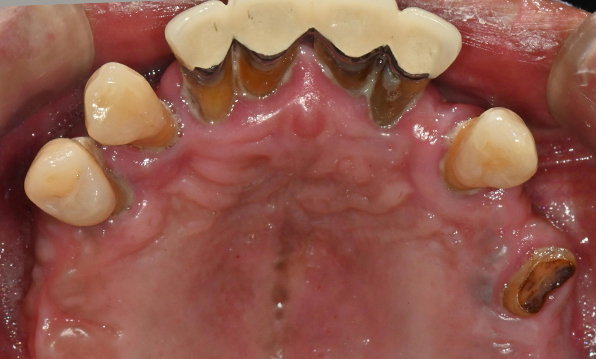

전체 임플란트

위 아래 치아가 정확하게 맞아야하는 고난이도 임플란트

임상 경험이 많은 숙련된 전문의의 섬세한 기술력이 중요합니다.

정확성 높은 식립의 노하우

전체 임플란트는 위턱과 아래턱의 교합, 잇몸뼈의 상태 및

얼굴 변화 등 모든 것을 고려해 식립해야 합니다.

이 때, 치조골 이식을 병행하여 잇몸뼈 재건 후 안정적인 임플란트 식립을 하고 있습니다.

치료기간 : 2021.04.12~2021.09.15